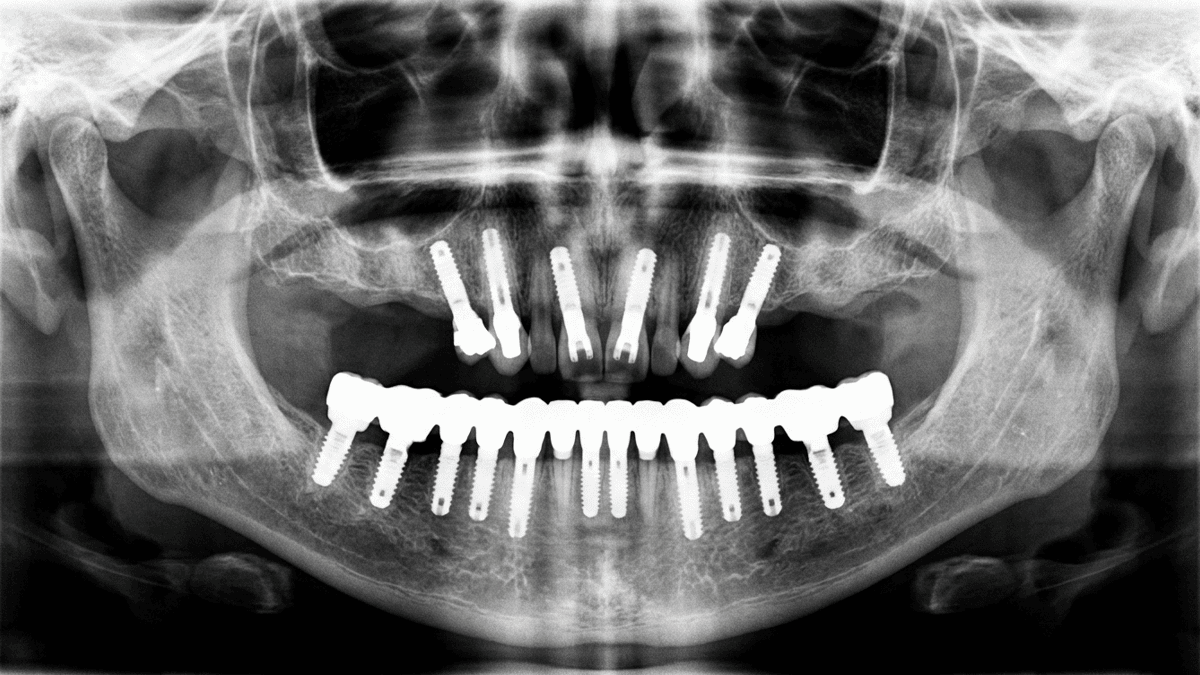

Имплантация All-on-6 на верхней челюсти: несъёмные зубы за один день даже при сильной атрофии кости

All-on-6 — что это за технология и как она работает

Название говорит само за себя: All-on-6 — это "всё на шести". Вся челюсть, все зубы — на шести имплантах. Не на двенадцати, не на восьми. Шесть точек опоры, и этого достаточно для полноценного несъёмного протеза.

Шесть имплантов распределяются по челюсти стратегически. Четыре — во фронтальном отделе, где кость обычно сохраняется лучше. Два — в боковых, под углом. Угловая установка — это не от лени хирурга, а продуманное решение. Когда имплант ставится наклонно, он "цепляет" больший объём кости и обходит те самые гайморовы пазухи.

Всё начинается с КЛКТ — конусно-лучевой компьютерной томографии. Это 3D-снимок вашей челюсти. Не плоский рентген, а полноценная трёхмерная модель. На ней видно всё: сколько кости осталось, где проходят нервы и сосуды, какой объём пазух.

Дальше — виртуальное планирование. Хирург в специальной программе "расставляет" импланты, подбирает их длину и диаметр, выбирает оптимальные углы. Это как репетиция операции, только на компьютере.

На основе этого плана изготавливается навигационный шаблон — пластиковая капа с отверстиями в нужных местах. Во время операции хирург работает через этот шаблон. Он физически не может поставить имплант "не туда" — отверстие не даст. Точность — до долей миллиметра.

Решение: протокол All-on-6 с птеригоидными имплантами. Установлено 4 импланта во фронтальном отделе + 2 птеригоидных. Операция заняла 2 часа 15 минут под седацией.